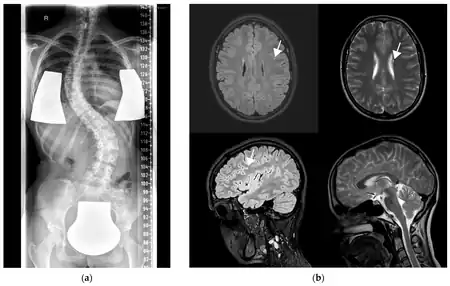

GOSR2-related progressive myoclonus ataxia, also known as Progressive myoclonic epilepsy type 6 is a rare genetic type of progressive myoclonus ataxia which is characterized by progressive myoclonic epilepsy with an early onset which is associated with generalized tonic-clonic seizures, petit mal seizures, and drop attacks, variable degrees of scoliosis, areflexia, high levels of creatine kinase serum, and late-onset cognitive decline.[1][2]